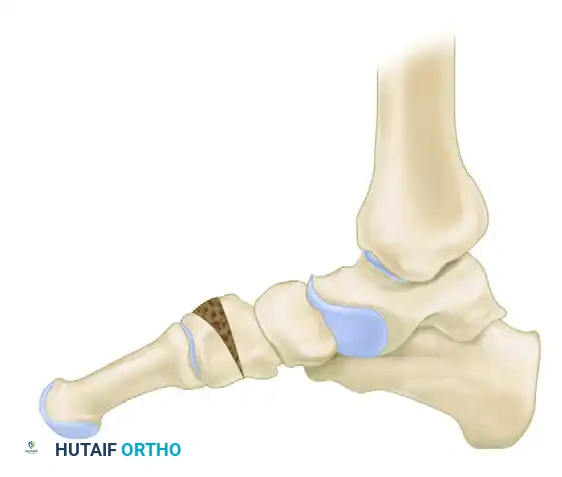

3. Prepare a structural bone wedge (typically tricortical iliac crest autograft or allograft, or a porous titanium wedge) measuring between 4 to 8 mm at its dorsal base, depending on the severity of the supinatus.

- Impact the wedge into the osteotomy site. Ensure the graft is flush with the dorsal cortex to prevent hardware irritation.

- Fixation is typically achieved using a dorsal locking plate, a staple, or crossed K-wires, depending on surgeon preference and bone quality.